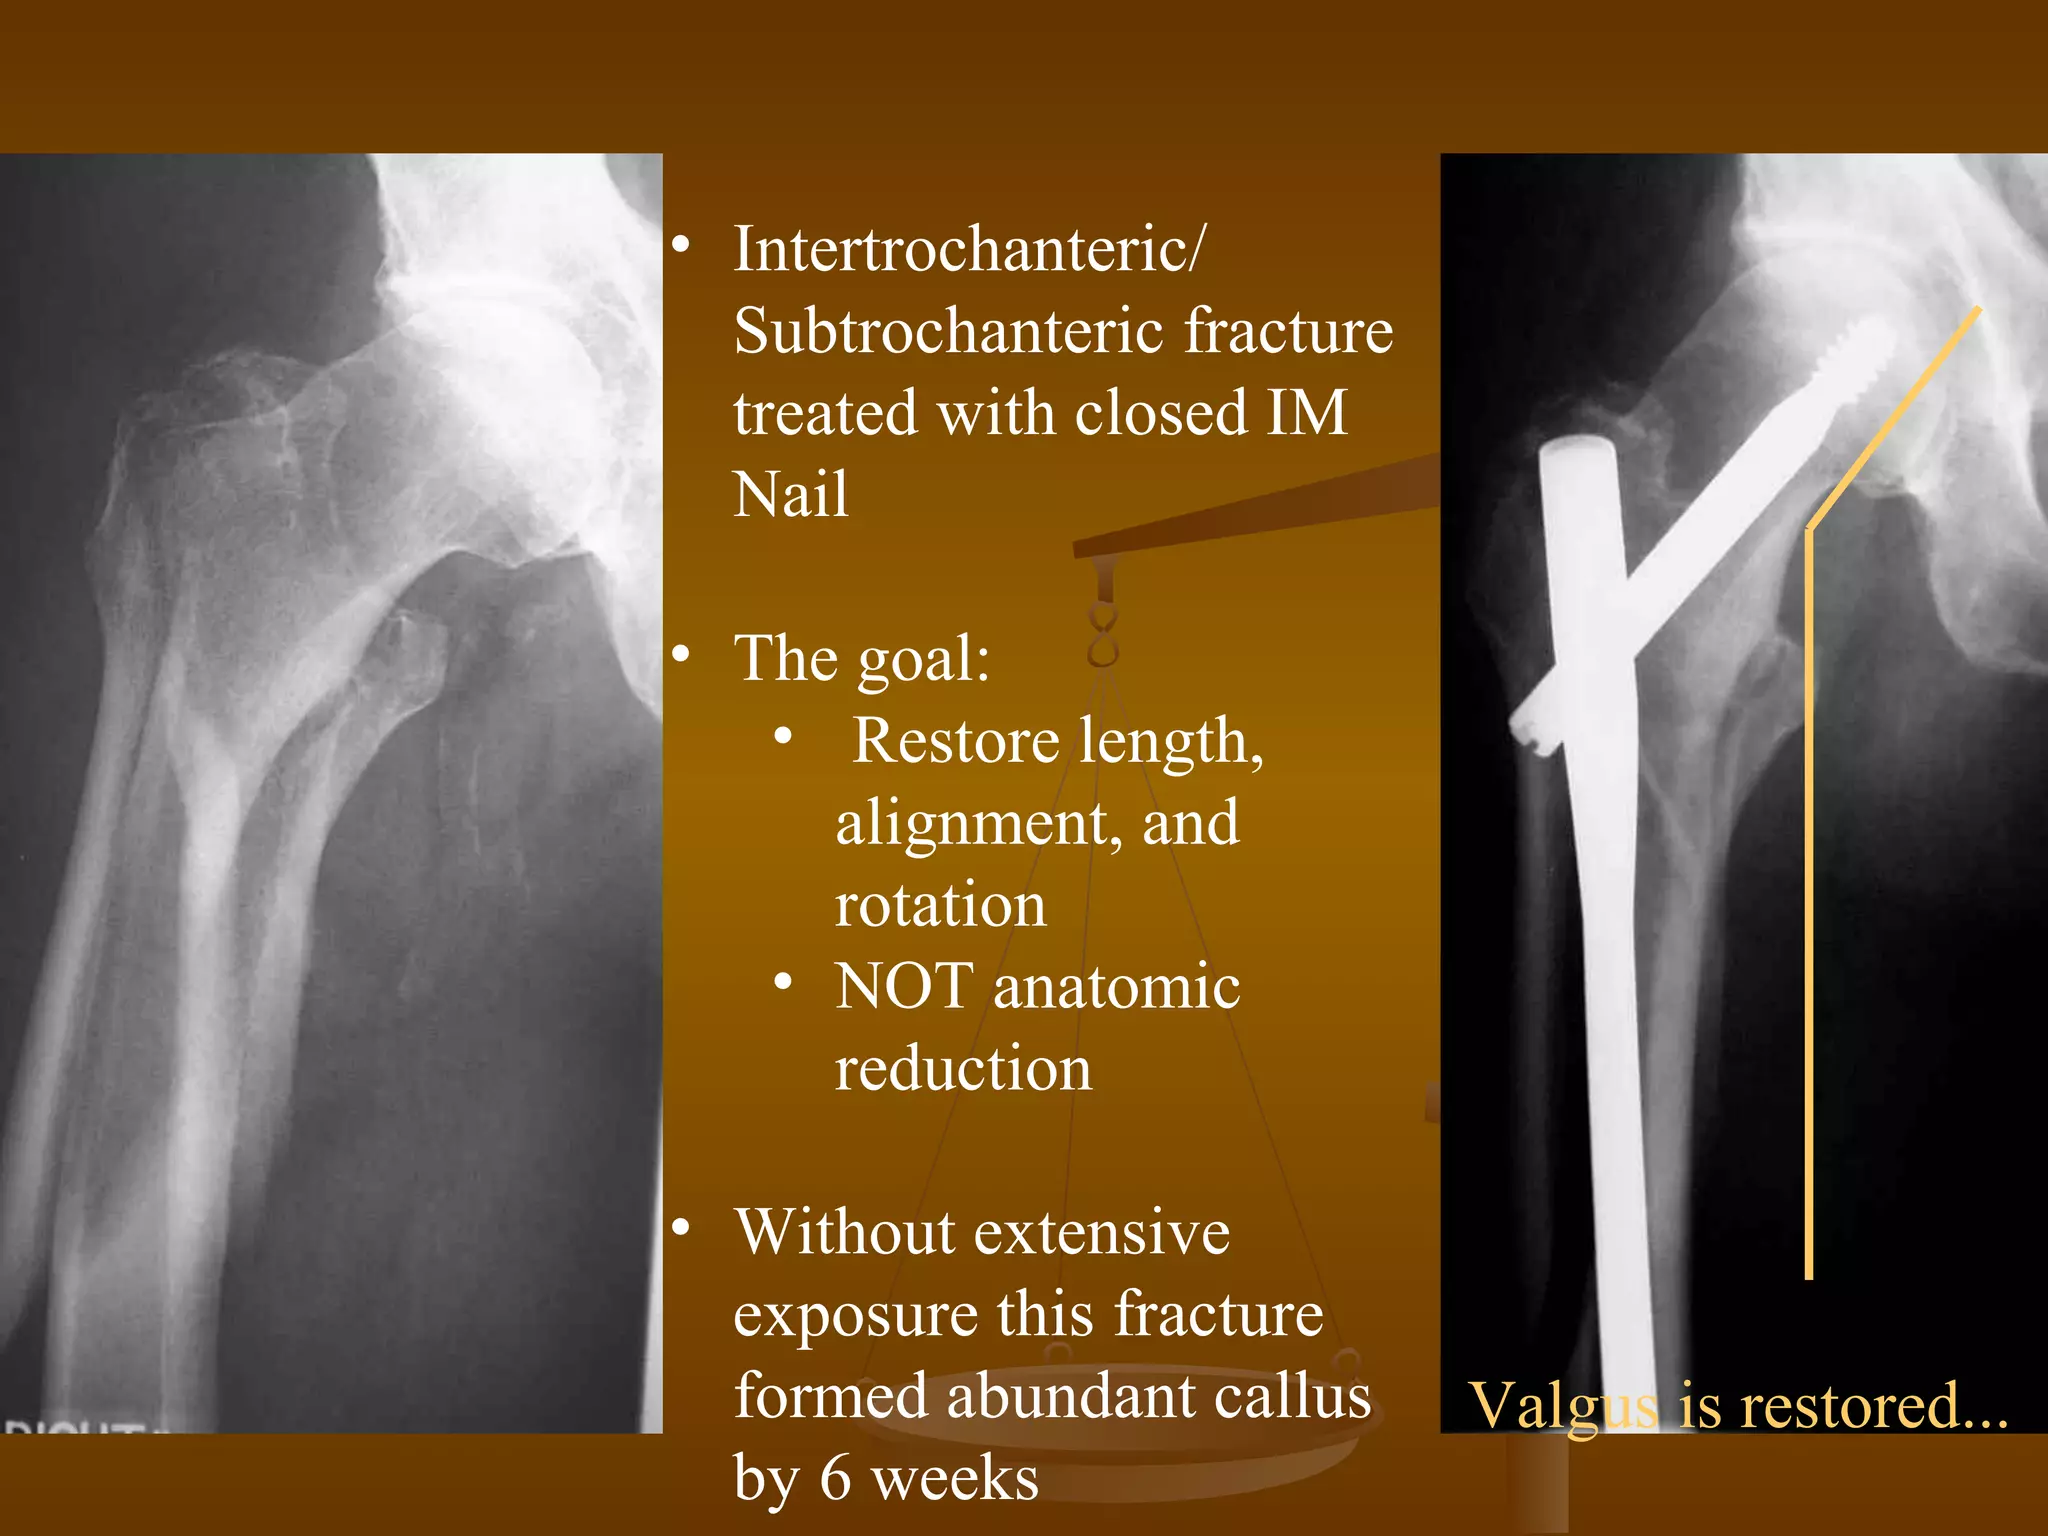

• Intertrochanteric/

Subtrochanteric fracture

treated with closed IM

Nail

• The goal:

• Restore length,

alignment, and

rotation

• NOT anatomic

reduction

• Without extensive

exposure this fracture

formed abundant callus

by 6 weeks

Valgus is restored...